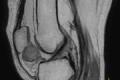

Виды МРТ суставов: какие суставы можно обследовать с помощью МРТ

Одним из самых распространенных видов диагностики с помощью магнитно-резонансной томографии является проведение МРТ суставов. Это диагностическое исследование с почти 100%-ной вероятностью поможет определить как и системные заболевания костной системы и суставов (а такие, к сожалению, в наше время встречаются все чаще), так и проблемы в отдельных ее узлах и органах (например, трещины, вывихи, переломы и пр.).